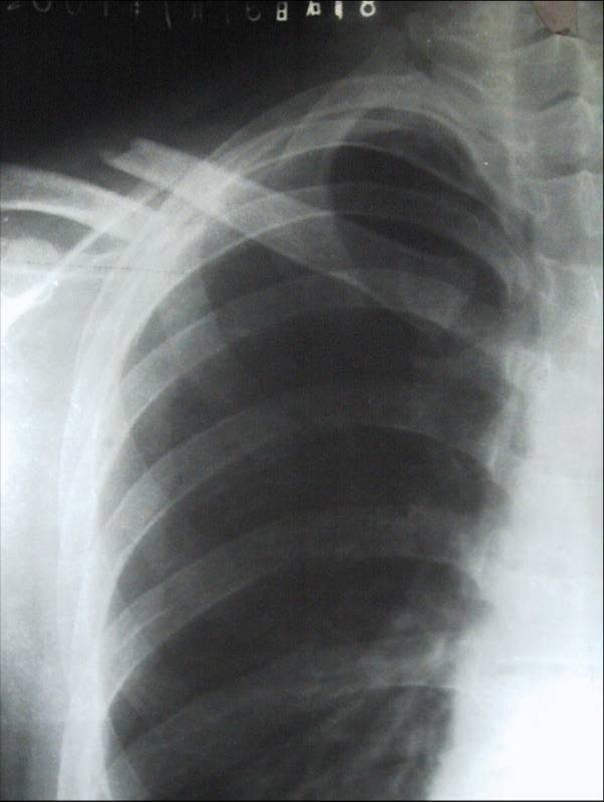

上肢骨折 上肢骨折概論 上肢骨折各論 鎖骨骨折 肱骨外科頸骨折 肱骨幹骨折 中文百科全書

與肱骨外科頸骨折或骨骺分離切開復位加壓螺絲釘內固定相關的文獻報道 醫學百科

上肢骨折 華人百科

上肢骨折 華人百科